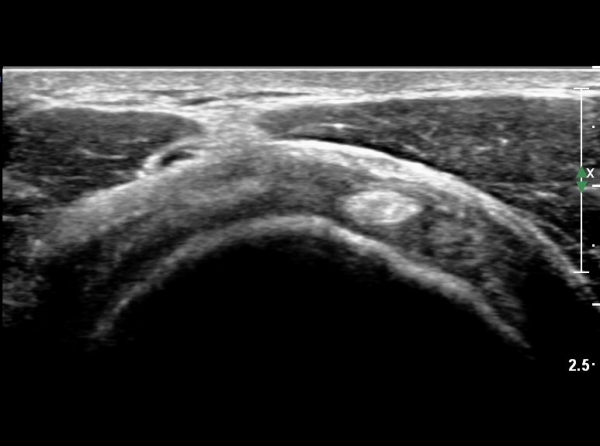

°ß°©ÇÏ±Ù°Ç Á¾´Ü¸ç°Ë»ç¿¡¼­ °Ç »óºÎ¿¡ ÀÌÁúÀûÀÎ ¿¡ÄÚ¸¦ º¸¿© °ß°©ÇÏ±Ù°Ç »óºÎ ºÎºÐÆÄ¿­ÀÌ ÃßÁ¤µÈ´Ù(»çÁø 3),

°ß°©ÇÏ±Ù°Ç È¾´Ü¸é°Ë»ç¿¡¼­ °Ç »óºÎ¿¡ ÀÌÁúÀûÀÎ ¿¡ÄÚ¸¦ º¸¿© °ß°©ÇÏ±Ù°Ç »óºÎ ºÎºÐÆÄ¿­ÀÌÃßÁ¤µÈ´Ù(»çÁø 5, 6, 7)